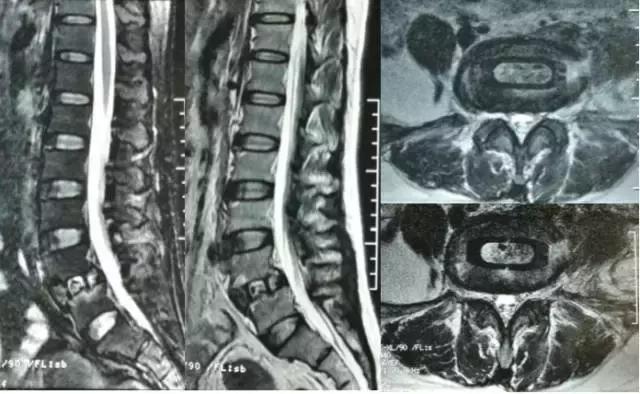

▲手术前

▲手术后MRI